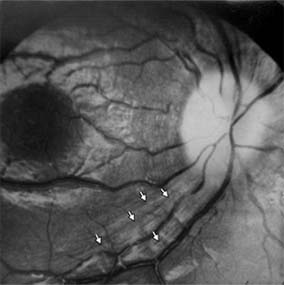

Optic atrophy (Figure 14-6) is a nonspecific response to optic nerve damage from any cause. Since the optic nerve consists of retinal ganglion cell axons, optic atrophy may be the consequence of primary retinal disease, such as retinitis pigmentosa or central retinal artery occlusion. Excavation of the optic nerve head (optic disk cupping) is generally a sign of glaucomatous optic neuropathy, but may occur with any cause of optic atrophy. Segmental pallor and attenuated retinal blood vessels are often the consequence of anterior ischemic optic neuropathy. Hereditary optic neuropathies usually produce bilateral temporal segmental disk pallor with preferential loss of papillomacular axons. Peripapillary exudates occur with optic disk swelling, due to papillitis, ischemic optic neuropathy, or papilledema, and may take longer to resolve. (The term "neuroretinitis" for the combination of optic disk swelling and retinal exudates, including a macular star, is a misnomer in that there is no inflammation of the retina, the exudates being a response to the anterior optic nerve disease. This may occur in demyelinative and other types of optic neuritis, anterior ischemic optic neuropathy, and papilledema. The term "neuroretinitis" is more reasonably applied if there is true inflammation of the retina and optic nerve [Figure 14-7].) Other helpful signs of prior disk edema are peripapillary gliosis and atrophy, chorioretinal folds, and internal limiting membrane wrinkling.

Figure 14-11

Figure 14-11: Retinal nerve fiber layer in demyelinating optic neuropathy of multiple sclerosis. The upper temporal nerve fiber bundles show multiple slit-like areas of thinning (arrows) representing retrograde axonal atrophy from subclinical disease in the optic nerve. Vision in the eye was 20/20.